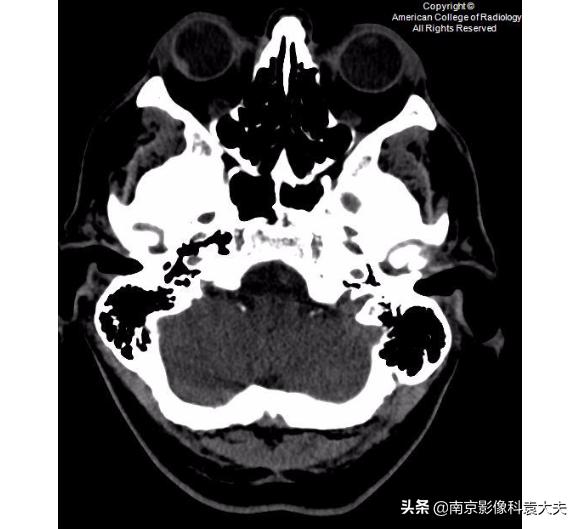

B:右侧眼球外侧的高密度提示出血,这往往是眼外伤的直接征象。

非对比增强CT(平扫)更低一层面显示沿右眼球外侧壁的高密度的眼内出血(箭头)。眼内出血可能是眼外伤的一

右眼矢状位非对比增强CT(平扫)显示前房(箭头)塌陷。这可以在角膜裂伤的情况下看到。